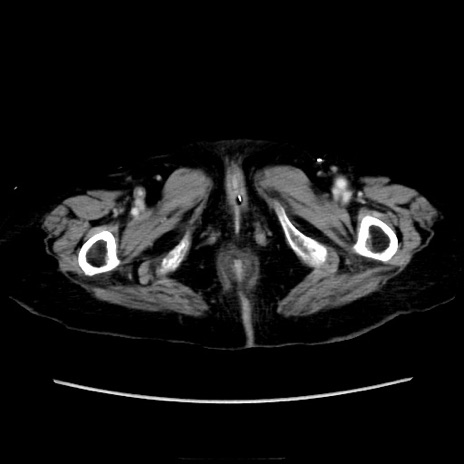

症例40(横断像)

横断像